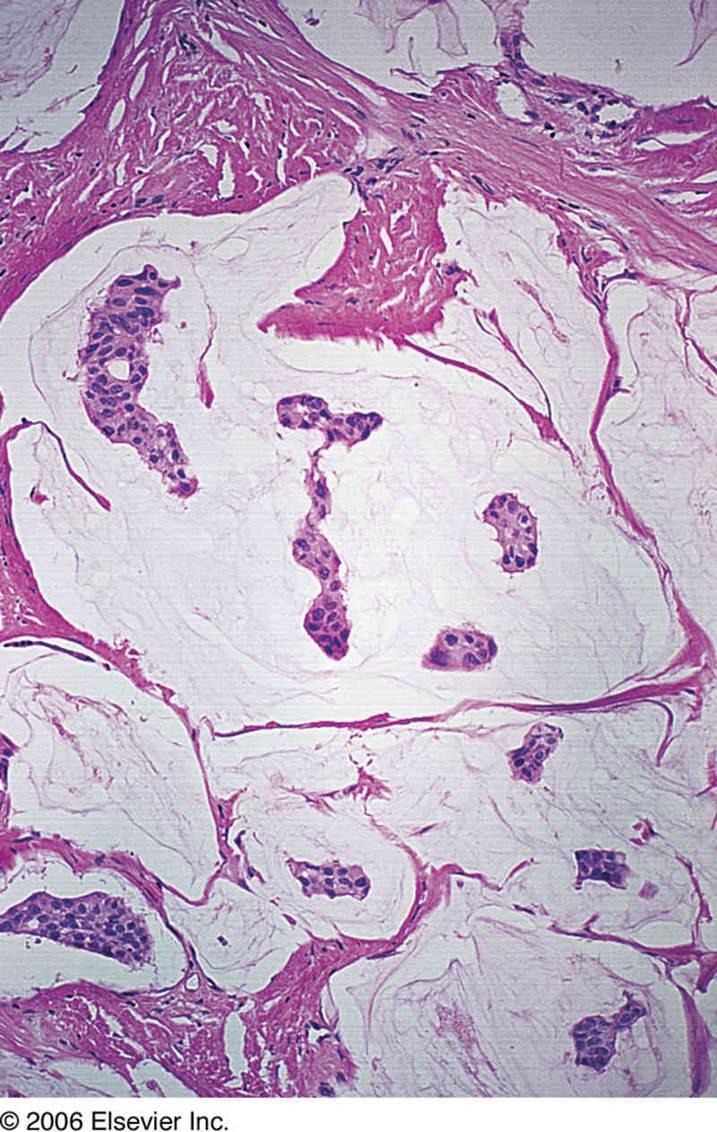

Mucinous: small islands of cells with lakes of mucin

Mucinous: lots of mucin and islands of cells